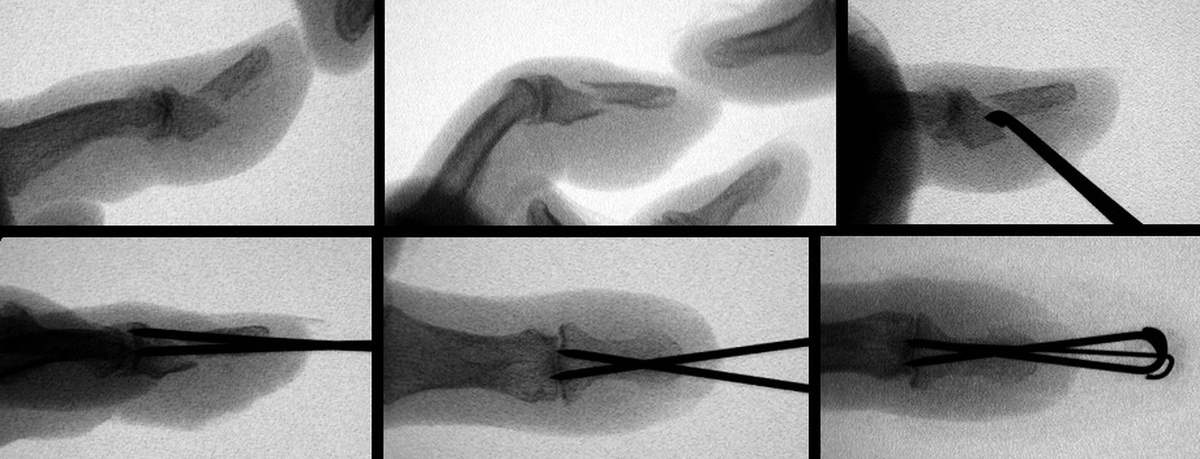

| Case 1. 6 week old grossly unstable distal phalanx fracture. Fracture reduced through a midline palmar approach and stabilized with extraarticular nonparallel Kirschner wires. |

| Exposure. |

| The K-wires were

bent to form a zone of overlap which was bonded

together with thermoplastic splint material. |

| Pins were removed

at 5 weeks with uneventful fracture healing. |